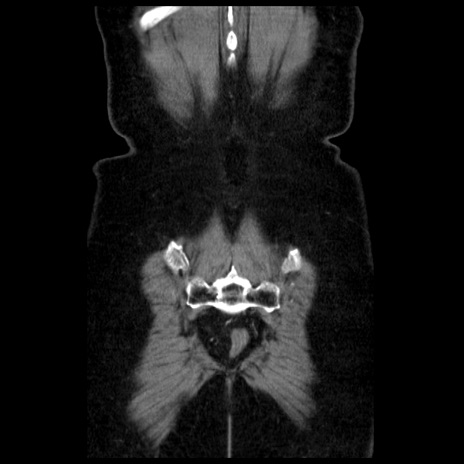

症例13(冠状断像)

【症例】70歳代女性

【主訴】腹痛、嘔吐

【現病歴】15時間程前(昨晩)より腹痛あり。今朝になっても症状の改善なく、嘔吐あり。腹痛も増悪あり、救急外来受診。

【既往歴】子宮癌全摘術後

【身体所見】意識清明、BP 121/72mmHg、P 74bpm、SpO2 100%(RA)、腹部:平坦・軟、腸雑音ほぼ聴取せず。下腹部・心窩部・臍左上に圧痛あり。反跳痛なし。

【データ】WBC 10600、CRP 0.15